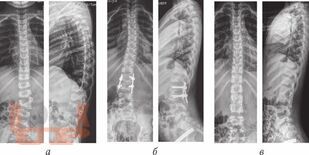

В монографии отражены современные подходы и принципы хирургического лечения пациентов детского возраста с вариантами врожденных пороков развития позвоночного столба, освещаются различные доступы и методы оперативного вмешательства при врожденных деформациях. Подробно описаны типы врожденных деформаций позвоночника при разных аномалиях развития позвонков, представлены современные классификации, темпы прогрессирования врожденного искривления при естественном течении врожденных кифозов, сколиозов и кифосколиозов. Отражены методы и история развития консервативного лечения врожденных деформаций позвоночника, современные взгляды на хирургические подходы к лечению врожденных пороков развития позвоночного столба. Представлены различные варианты металлоконструкций, некоторые из которых разработаны самими авторами (позвоночные, реберно-реберные, реберно-позвоночные системы), и технологии их применения. Подробно изложены результаты хирургического, в том числе этапного, лечения пациентов с врожденными деформациями позвоночника, дана оценка эффективности различных методик оперативного вмешательства. В книге также представлены клинические наблюдения результатов лечения детей с врожденными искривлениями позвоночного столба, описаны особенности послеоперационного ведения пациентов с данной патологией. Представлены и проанализированы осложнения, которые встречаются прихирургической коррекции врожденных деформаций позвоночника, определены причины их возникновения. Отражены принципы и подходы к лечению детей с врожденными пороками развития позвонков в сочетании с аномалиями развития спинного мозга и позвоночного канала.